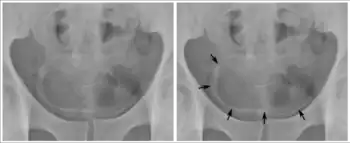

Imaging

Imaging modalities such as X-rays, ultrasound, computed tomography (CT), and magnetic resonance imaging (MRI) can be utilized to evaluate for severity of schistosomiasis and damages of the infected organs.[53] For example, X-ray and CT scans of the chest can be used to detect lesions in the lungs from pulmonary schistosomiasis, and pelvic X-ray can reveal calcification of the bladder in chronic urinary schistosomiasis.[53] Ultrasound may be used to look for abnormalities in the liver and spleen in hepatosplenic schistosomiasis, and CT scan of the liver is a good tool to look for calcification in the liver associated with S. japonicum infection.[53] CT scan can also be used to assess damages from the schistosomiasis infection in the intestinal, urogenital, and central nervous system.[53] MRI is used to evaluate schistosomiasis of the central nervous system, liver, and genital.[53]